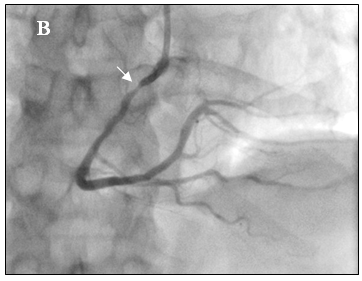

Tại cấp cứu bệnh nhân được chẩn đoán nhồi máu cơ tim cấp vùng hoành giờ thứ 2, block A-V độ 3, có chỉ định chụp mạch vành cấp cứu. Kết quả chụp mạch vành cho thấy hẹp nặng lan tỏa nhiều đoạn ở cả động mạch vành trái (hình 2a) và động mạch vành phải (hình 2b).

Hình 2a: Dấu mũi tên trắng cho thấy nhiều chổ hẹp ở nhánh LCX, OM và LAD

Hình 2b: Hệ mạch vành ưu thế phải, hẹp lan tỏa RCA

Tại phòng thông tim huyết áp bệnh nhân thấp 80/60mmHg nên chúng tôi không dùng Nitroglycerin. Sau khi chụp thấy hẹp nặng lan tỏa ở cả ba nhánh của động mạch vành, không loại trừ do co thắt nên chúng tôi đã tiến hành bơm 500µg Nitroglycerin vào động mạch vành. Kết quả chụp lại hiện tượng trên hoàn toàn biến mất, động mạch vành phải và trái thâm nhiễm nhẹ nhưng đều có kích thước lớn hơn nhiều so với ban đầu, dòng chảy TIMI 3 (hình 3a-3b), đồng thời huyết áp của bệnh nhân cũng cải thiện rõ 120/80 mmHg.

Hình 3a: Nhánh LCX, OM và LAD sau khi bơm Nitroglycerin

Hình 3b: Nhánh RCA sau khi bơm Nitroglycerin.